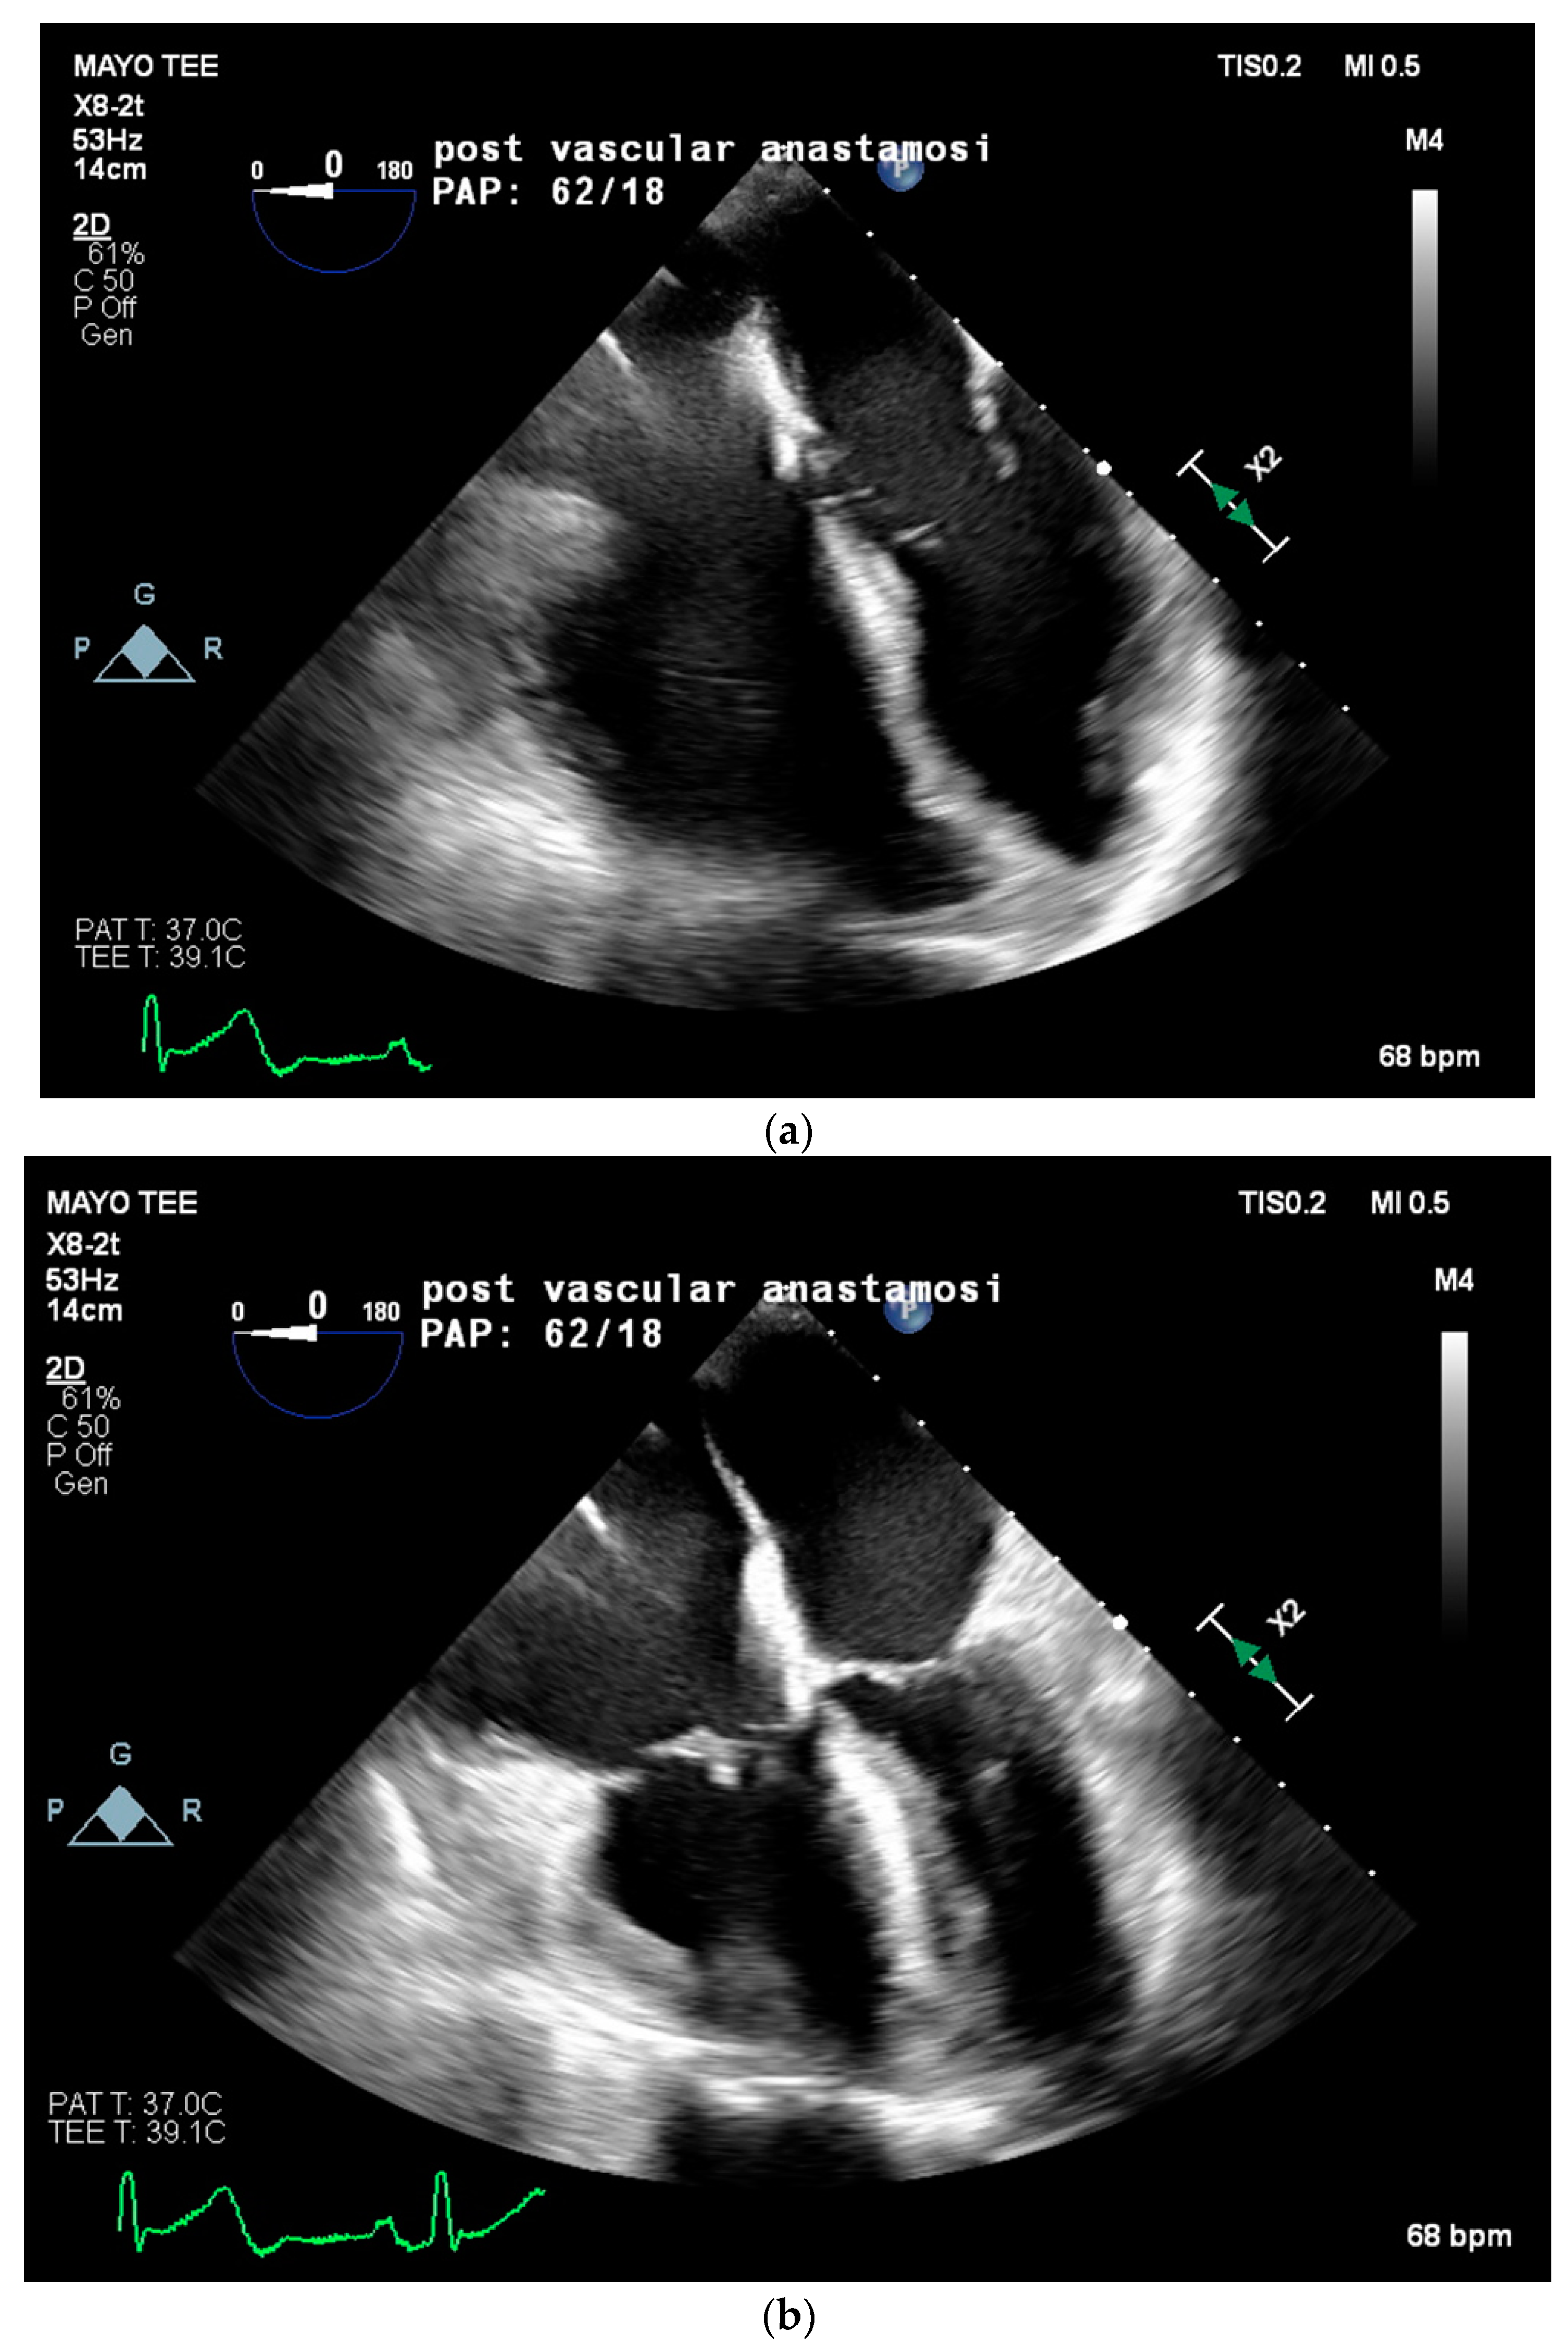

Two weeks later, in mid-February, the patient presented to the emergency department for worsening dyspnea. A repeat TTE showed worsening pulmonary hypertension with an estimated RVSP of 85 mmHg, a mPAP of 56 mmHg, moderate tricuspid regurgitation, and a moderately enlarged right ventricular chamber size with borderline contractile dysfunction. Due to the severity of symptoms and lack of curative options, multidisciplinary discussions concluded the plan for the patient to proceed with LT on preemptive VA ECMO support at the end of February. Twenty-four hours prior to the LT, the patient was placed on VA ECMO with a 23 French right internal jugular venous cannula, a distal cannula tip advanced to the infra-hepatic inferior vena cava (IVC), and a 21 French right axillary arterial cannula. ECMO support was initiated, achieving 2.5 L/min of flow. The patient’s PAP significantly improved from systolic in 70 mmHg to approximately 50 mmHg. The day following ECMO cannulation, a liver became available, and the patient returned to the operating room for transplantation. The intraoperative anesthetic plan included general anesthesia and peripheral VA ECMO. Radial and brachial arterial lines, a central venous line with PAC, and a hemodialysis catheter were placed. Physicians from Transplant Anesthesiology, Cardiac Anesthesiology, Transplant Surgery, and Cardiothoracic Surgery teams were present throughout the procedure. TEE was used to monitor cardiac function and guide ECMO flows throughout the procedure. VA ECMO flows were maintained at a minimum of 1.5 L/min to minimize clotting and serial activated clotting times (ACT) were monitored every 30 min and maintained between 170 to 220 s. No anticoagulation was required throughout the case due to the patient’s baseline coagulopathy. The patient was kept on a low-dose norepinephrine infusion (less than 0.05 mcg/kg/min) and 0.04 units/min of vasopressin infusion throughout the procedure. Intraoperative TEE on VA ECMO revealed a severely enlarged right ventricle, borderline reduced right ventricular systolic function, patent foramen ovale, mild tricuspid regurgitation, and normal left ventricular ejection fraction. Immediately following reperfusion, PAP significantly increased from a systolic of 40 mmHg to 78 mmHg, with TEE showing severe right ventricular systolic dysfunction and impending RV collapse (refer to Figure 2). VA ECMO flows were increased from 1.6 to 2.4 L/min to assist the RV, in lieu of inotropic support, with improvement in right ventricular systolic function and eventual normalization. Intravenous calcium chloride (2 g) was given for reperfusion with no further intraoperative need for inotropic or vasopressor support. The patient remained hemodynamically stable throughout the remainder of the procedure. Prior to leaving the operating room, TEE images noted normal right ventricular systolic function, unchanged moderate to severe right ventricular dilation, and preserved left ventricular ejection fraction. The patient was then transported to the ICU on VA ECMO with inhaled nitric oxide, inotropic, and vasopressor support, including norepinephrine at 0.04 mcg/kg/min and vasopressin at 0.04 units/min. On postoperative day 4, the patient was deemed ready for VA ECMO decannulation and returned to the OR for decannulation. Unfortunately, her postoperative course was mired with complications including worsening PAP, continued hemodynamic instability necessitating inotropic and vasopressor support, worsening hypoxia, and severe coagulopathy necessitating several transfusions. The patient ultimately expired in the ICU 6 weeks post LT at the beginning of March 2022 from refractory hypoxia and hypotension leading to asystole.

Figure 2. Following cross-clamp removal on reperfusion, pulmonary artery pressures significantly increased from a PA pressure of 40 mmHg to 78 mmHg with severe right ventricular systolic dysfunction. Images taken during diastole (a) and systole (b) are shown to appreciate the degree of right ventricular dysfunction present immediately following reperfusion. Septal bowing into the left ventricle from severe right-sided pressure overload can be appreciated in systole (b).